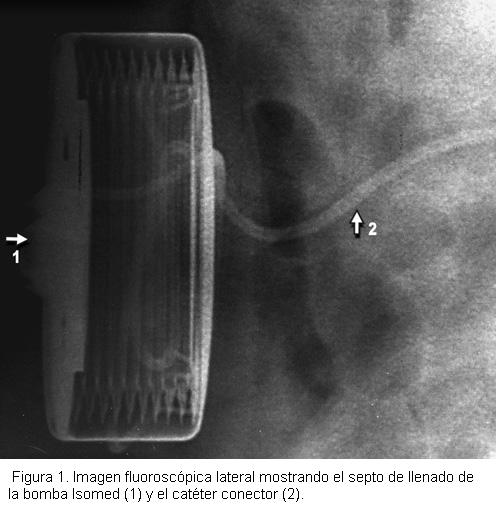

El procedimiento se realizó bajo anestesia general, se efectuó una incisión paravertebral derecha a nivel L2-L3, se abordó el espacio subaracnoideo con una aguja de Tuohy y se introdujo el extremo del catéter hasta T10.

Se colocó la bomba a nivel subcutáneo en un bolsillo supra-aponeurótico paraumbilical derecho (figura 1), y mediante una tunelización bajo la piel se pasó el catéter conector que se unió al extremo distal del catéter intratecal (figura 2). Se llenó la bomba con 3 ml (30 mg) de sulfato de morfina al 1% sin conservantes y 57 ml. de suero fisiológico, se realizó la fijación del implante y se cerró la piel por planos.